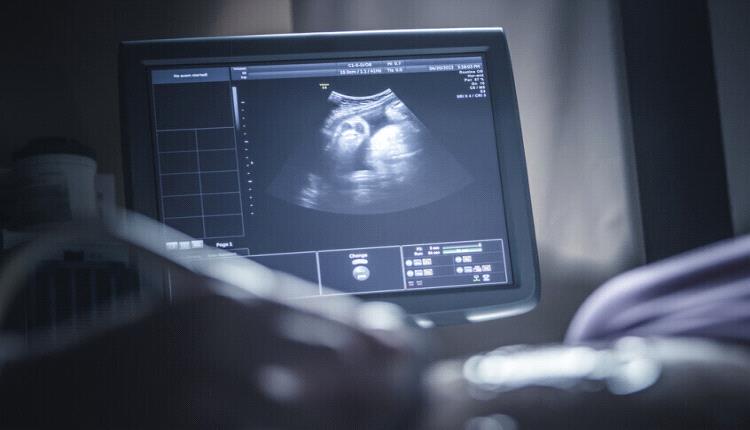

ولد طفل في الهند بحالة طبية غريبة ونادرة للغاية، حيث كان يحمل بداخله جنينين آخرين.

وفي الشهر الماضي، زارت امرأة تبلغ من العمر 32 عاما في الهند مستشفى محليا لإجراء فحص روتيني أثناء حملها في الأسبوع الخامس والثلاثين.

وعلى الرغم من أن فحوصاتها السابقة كانت طبيعية، اكتشف الأطباء "هيكلا إضافيا يحتوي على عظام" في بطن الجنين الذكر.